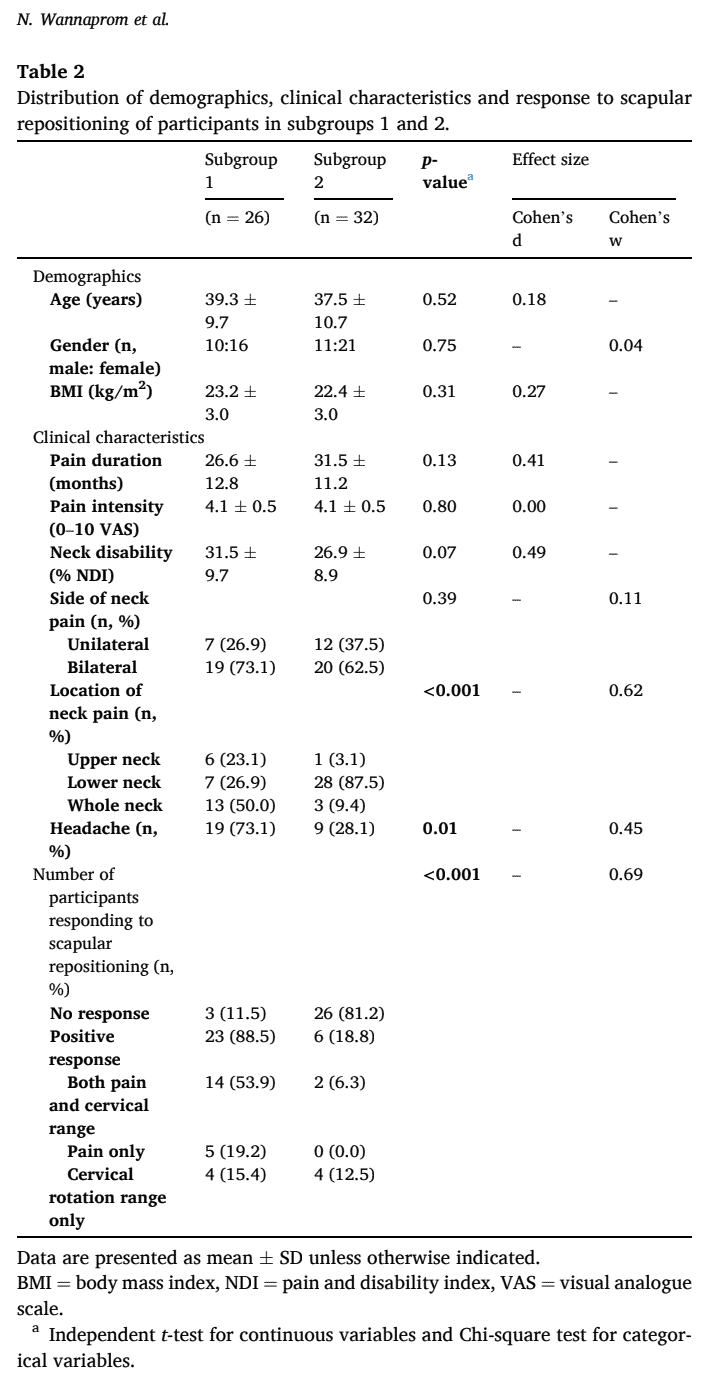

Bei der aktuellen Studie erklärten sich 58 Teilnehmer zur Teilnahme bereit. 29 von ihnen waren Responder, da sie bereits zuvor positive Ergebnisse bei Nackenschmerzen und Bewegungsumfang nach der Skapulierumlagerung erzielt hatten. Neunundzwanzig Personen wurden als Non-Responder eingestuft. Die Stichprobe bestand zu etwa 60 % aus Frauen, die im Durchschnitt 38 Jahre alt waren (+/- 10 Jahre). Die Intensität der Nackenschmerzen betrug 4,1 (+/- 0,5) auf der VAS und der Nackenschmerz-Index lag bei 29,0 (+/-9,4).

Auf der Grundlage der 3D-Messungen wurden zwei Untergruppen ermittelt. In der Untergruppe 1 zeigten die Teilnehmer eine stärkere Klavikularretraktion und eine Skapularrotation nach unten. In der Untergruppe 2 war das Schlüsselbein stärker angehoben und das Schulterblatt stärker nach vorne gekippt und nach innen gedreht. Die Untergruppe 1 berichtete häufiger über Kopfschmerzen und mehr Schmerzen im oberen oder ganzen Nacken, während die Teilnehmer der Untergruppe 2 mehr Schmerzen im unteren Nackenbereich angaben. Bei allen anderen Ergebnissen (demografische Daten, Intensität, Dauer und Behinderung der Nackenschmerzen) waren die Untergruppen gleich.

Was die Reaktion auf die Skapulierumlagerung bei Nackenschmerzen betrifft, so ergab diese Studie, dass 88,5 % der Teilnehmer in Untergruppe 1 positiv reagierten, während 81,2 % in Untergruppe 2 nicht reagierten.

Rede mit mir über Nerds

Ein guter Aspekt dieser Studie war, dass sie viele Details lieferte, die für die Reproduktion dieser Studie erforderlich sind. Es wäre interessant zu sehen, was randomisierte, kontrollierte Studien über diese Skapulierpositionierung bei Nackenschmerzen ergeben. In dieser Studie wurden 2 Untergruppen von Nackenschmerzpatienten auf der Grundlage unterschiedlicher Skapularausrichtungen gefunden. Wichtig ist jedoch, dass die Untergruppen keine Unterschiede in Bezug auf Demografie, Intensität, Dauer und Behinderung der Nackenschmerzen aufwiesen. Wir können also davon ausgehen, dass die Personen recht homogen waren, abgesehen von ihren anatomisch unterschiedlichen Ausrichtungen im Schultergürtel und der Lokalisierung der Nackenschmerzen. Diese Untergruppen wurden auf der Grundlage großer Effektstärken identifiziert.

In dieser Studie wurden bei Patienten mit chronischen Nackenschmerzen auf der Grundlage von 3D-Messungen der Skapulaausrichtung 2 verschiedene Untergruppen identifiziert. Die Gruppe, die eine stärkere Abwärtsrotation des Schulterblatts und eine Retraktion des Schlüsselbeins aufwies, sprach auf die Umlagerung des Schulterblatts an, während die Gruppe, die eine stärkere Anhebung des Schlüsselbeins, eine Innenrotation und eine anteriore Neigung des Schulterblatts aufwies, bei Nackenschmerzen nicht auf die Umlagerung des Schulterblatts ansprach. Außerdem hatten diejenigen, die auf die Behandlung ansprachen, mehr Schmerzen im oberen Nackenbereich und Kopfschmerzen, während diejenigen, die keine gute Reaktion zeigten, mehr Schmerzen im unteren Nackenbereich hatten. Dies kann eine wichtige Rolle bei der Auswahl Ihrer Behandlungsoptionen für diese Patienten spielen.